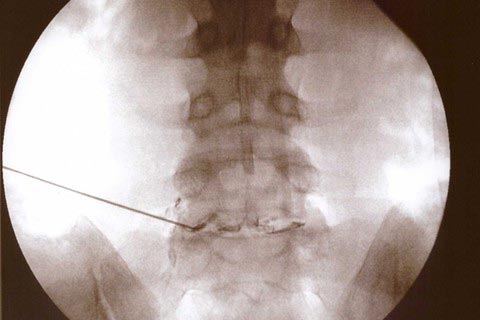

Γενικά η δισκοπλαστική (discogel) είναι μία τεχνική που απαιτεί κατά τη γνώμη μας εμπειρία από τον χειρουργό σε μικροεπεμβατικές τεχνικές, άριστη γνώση τοπογραφικής ανατομικής και στερεοταξίας της σπονδυλικής στήλης, και ασφαλώς εξειδικευμένο και κατάλληλο εξοπλισμό, δηλαδή κατάλληλο τραπέζι (κρεβάτι) χειρουργείου (με έκκεντρη στήριξη, δηλαδή την κολώνα που το στηρίζει στο άκρο του) ώστε να μπορεί να συνδυαστεί με το φορητό ακτινοσκοπικό μηχάνημα (c-arm) και να έχει ο χειρουργός πλήρη εικόνα της οσφύος ανά πάσα στιγμή ώστε να καταφέρει να τοποθετήσει τη βελόνα στην επιθυμητή περιοχή, επίσης ειδικό πλαίσιο (όπως το cabine frame) στο οποίο τοποθετείται ο ασθενής και το οποίο επιτρέπει κατά το δυνατόν την μείωση της οσφυϊκής λόρδωσης (της φυσιολογικής κούρμπας δηλαδή της μέσης) με αποτέλεσμα να δημιουργούνται καλύτερες συνθήκες προς διευκόλυνση της τοποθέτησης της βελόνης στο επιθυμητό σημείο. Μάθετε περισσότερα

Εγχέεται υπό ακτινοσκόπηση με τοπική αναισθησία με λεπτή βελόνα μέσα στον μεσοσπονδύλιο δίσκο. Μάθετε περισσότερα

Το νέο της υπόθεσης είναι πιο πολύ η κλίση του φορητού ακτινοσκοπικού μηχανήματος (c-arm) ώστε να είναι ορατό το τρήμα (εξ ου και διατρηματική) ώστε να αλλάξει η γωνία της εισόδου της βελόνας στον δίσκο κατά λίγες μοίρες τόσες όσες απαιτείται για την επίτευξη του σκοπού μας.